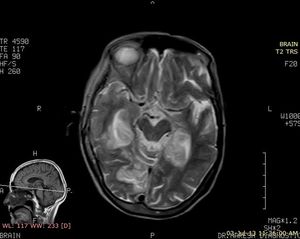

Case History: Four-year-old patient with complaints of altered sensorium.